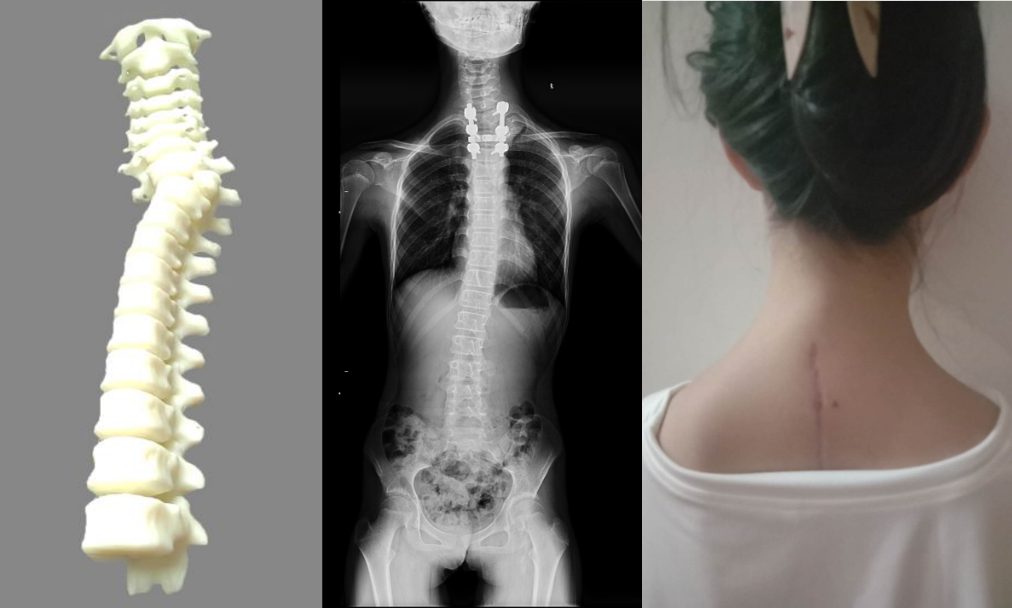

小张入院后,张文财细心地给她做了详细的脊柱检查,并将脊柱模型通过先进的3D打印技术呈现出来,与患者家属深入浅出地讲解了通过手术矫正的治疗方案。

经过详细的检查后,张文财主任团队决定给患者行T2半椎体切除+脊柱畸形矫形术。术前,该团队利用3D打印技术,将患者的脊柱按照1:1的比例打印成模型。

张文财介绍,3D打印可以让术者更加清晰、直观地观察局部的解剖结构以及与神经丛、血管束的毗邻关系,与邻近内脏器官的三维关联等。其次,在3D打印的骨骼模型上可以进行手术模拟,以反复论证并确认最佳手术方案、降低实际的手术时间和减少术中出血。另外,3D打印的模型可以使医生和患者更加直观地进行术前沟通,包括具体手术方式以及术中可能遇到的困难、术后可能的并发症等,提高了整体治疗的依从性。